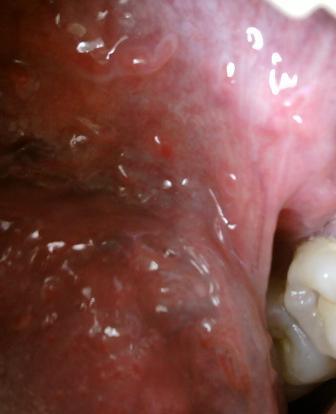

石家庄九州皮肤病医院 > 尖锐湿疣 > > > 尖锐湿疣会不会遗传尖锐湿疣发病原因是比较复杂的,具有传染性,但是是不会遗传的,主要是通过直接接触传染,间接接触传染以及母婴传染。

尖锐湿疣会不会遗传当确诊之后应该及时去医院进行治疗,初期对于疾病的治疗和康复是很关键的,现在疾病是比较多发的,医学上对于疾病的诊治也是比较重视的,治方法在逐步增多,选择适合的治疗方法,疾病才能够比较迅速的得到治疗。疾病的治疗是需要时间的,因此广大患者朋友们要坚持。